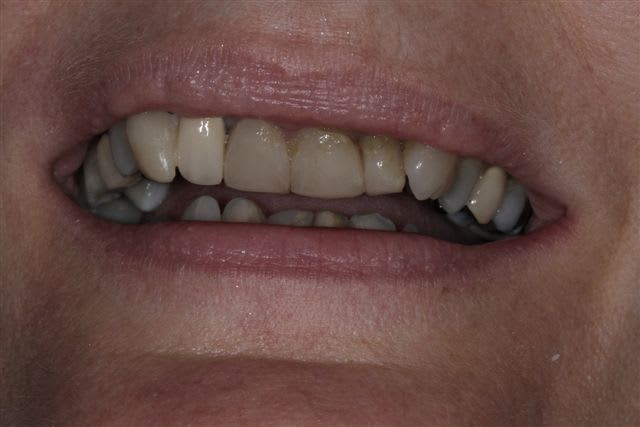

N'hésitiez pas çà me donner votre avis, patiente 47 ans ne supporte plus ses antérieurs, maquillées à la résine il y a quelques années.

Pas de demande concernant l'occlusion, ni les postérieurs, à fait des économies et veux s'offrir "un sourire", sur fond propre budget envisageable au départ 4000€

Vu les axes actuels des antérieures, soit tu gardes la même forme et les mêmes axes et tu auras de dents assorties mais pas vriament plus esthétiques. Sinon c'est ortho et la totale. Si tu changes la forme sans amélioration de l'esthétique ce sera l'echec mécanique assuré.

Je suis assez d'accord avec Ceramik, ce qui me saute aux yeux,outre l'esthétique bien sur, ce sont les courbes occlusales de la patiente, notamment secteur 2 et 3 en postérieurs(26 ne semble pas en occlusion, et 27 sur une pointe).

Le secteur antérieur doit donc supporter pas mal de contraintes... d'autant plus que le guide incisif semble assez fermé.

Perso, je ne toucherai à rien en antérieur,( d'autant plus avec du tout céram) tant que les courbes postérieures ne sont pas rétablies.